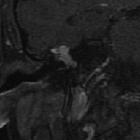

- congenital cholesteatoma

- no enhancement on post-contrast T1 MRI